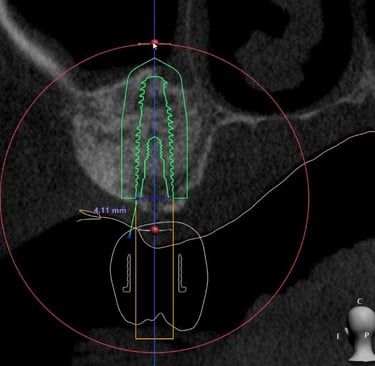

Pouco osso? A cirurgia guiada pode ser a solução.

Mesmo quando há pouca quantidade de osso, muitas vezes não é preciso fazer enxerto.

Com o uso de tecnologia digital em 3D, a cirurgia guiada permite planejar com precisão milimétrica a posição dos implantes, aproveitando ao máximo o osso disponível.

Esse planejamento detalhado também possibilita desviar de estruturas importantes, como o canal mandibular (por onde passa um nervo sensível) e o seio maxilar (uma cavidade natural próxima aos dentes superiores), tornando o procedimento mais seguro e previsível.

O resultado? Cirurgias mais rápidas, com recuperação mais tranquila e excelentes resultados — mesmo em casos que antes pareciam difíceis.

Caso da cirurgia guiada dispensando o enxerto - Imagens originais — nenhuma contém retoques